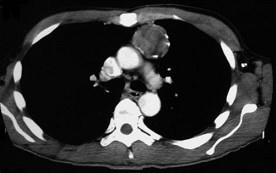

问题 47岁,男,腹泻、体重下降,伴有重症肌无力,请结合胸片和CT选择最可能的诊断 ( )

选项 A、纵隔血肿 B、错构瘤 C、胸腺瘤 D、淋巴瘤 E、胸腺增生

答案 C